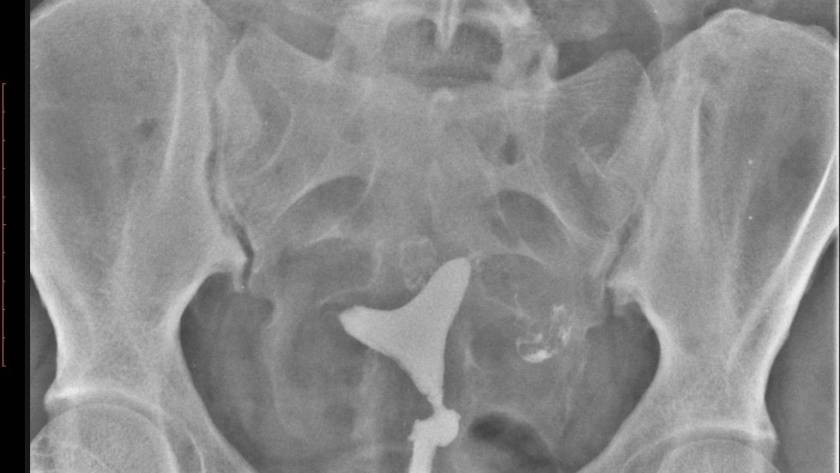

يتم إجراء HSG لتشخيص ما إذا كانت العقم ناتج عن المرأة. هيكل الرحم. يتبين ما اذا كانت الأنابيب مفتوحة. إذا كان هناك التصاق وتضيق وانسداد ، يمكن فتح الانابيب…